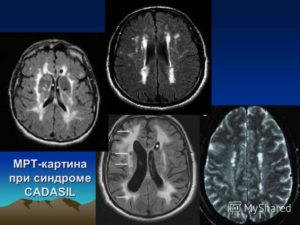

Рассеянный склероз имеет уникальную картину на МРТ: на сагиттальных срезах виден пунктир над третьим желудочком, служащий ранним признаком заболевания. Для рассеянного склероза также характерно образование пространств Вирхова-Робина — очаги нервной ткани с пониженной плотностью вокруг сосудов.

При рассеянном склерозе наблюдаются множественные гиперденсивные очаги.

| Рассеянный склероз | Очаги повышенной интенсивности сигнала в белом веществе, преимущественно перивентрикулярно, различной формы и размера. | Инфекционные заболевания ЦНС, лейкодистрофии |